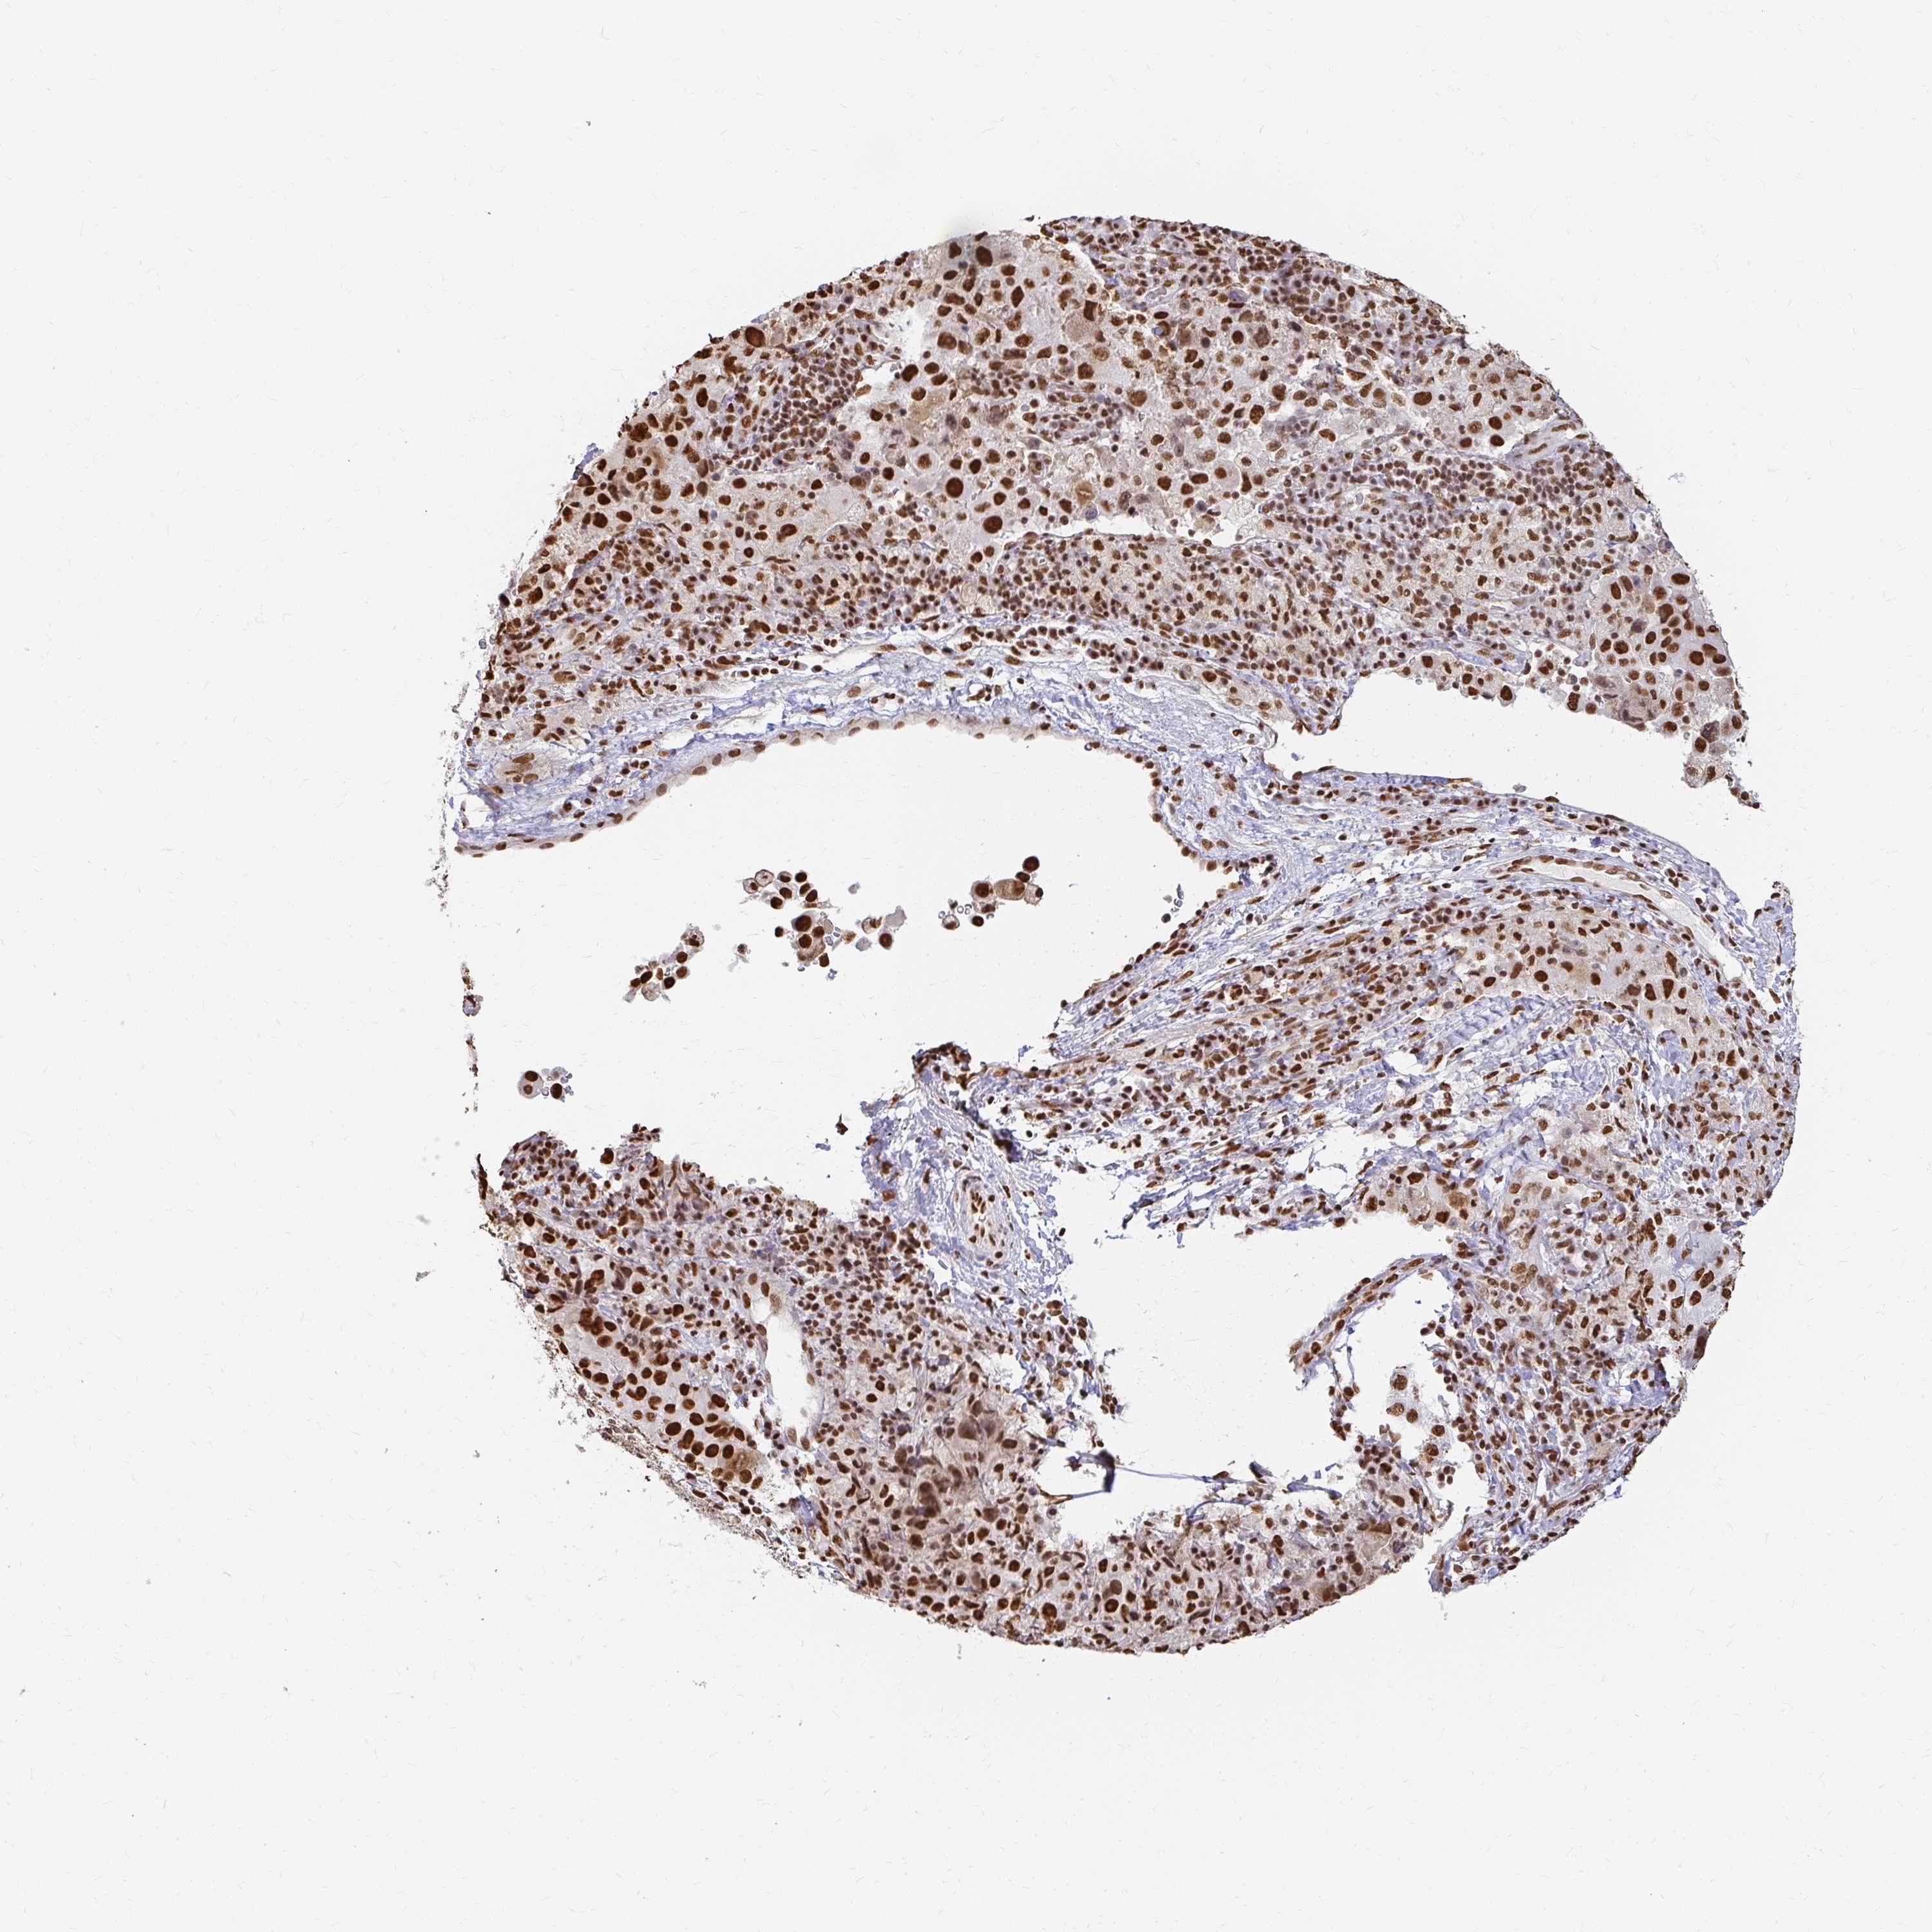

MELANOMA - Protein expressioni

A mouse-over function shows sample information and annotation data. Click on an image to view it in a full screen mode. Samples can be filtered based on level of antibody staining by selecting one or several of the following categories: high, medium, low and not detected. The assay and annotation is described here.

Note that samples used for immunohistochemistry by the Human Protein Atlas do not correspond to samples in the TCGA dataset.

Antibody stainingi

Antibody staining in the annotated cell types in the current human tissue is reported as not detected, low, medium, or high, based on conventional immunohistochemistry profiling in selected tissues. This score is based on the combination of the staining intensity and fraction of stained cells.

Each image is clickable and will lead to virtual microscopy that enables deeper exploration of all samples and also displays staining intensity scores, fraction scores and subcellular localization as well as patient and tissue information for each sample.

Antibody HPA041057

Antibody HPA058707

Antibody CAB011532

Staining

High

Medium

Low

Not detected

Intensity

Strong

Moderate

Weak

Negative

Quantity

>75%

75%-25%

<25%

None

Location

Nuclear

Cytoplasmic/membranous

Cytoplasmic/membranous,nuclear

Malignant melanoma, NOS

Malignant melanoma, Metastatic site